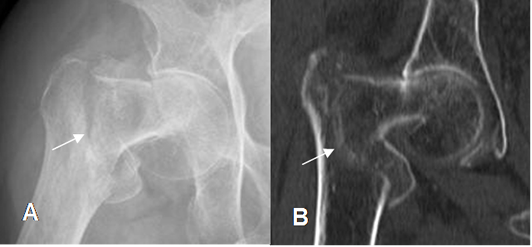

Fig 54. Fractura intertrocantérica.

A: Rx AP y B: TAC reconstrucción coronal. Fractura desplazada.